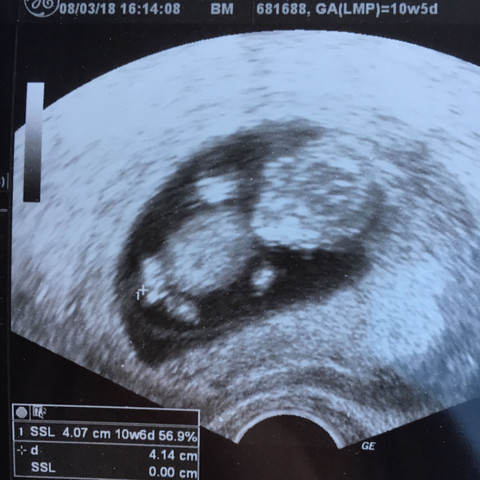

Ultraschall geschlecht junge falsch. Viele Eltern interessiert es brennend das Geschlecht ihres Kindes schon vor der Geburt zu erfahren. Nub theorie junge falsch - riesenauswahl an markenqualitä. Bei mir sagte der Harmony-Test dass es ein Junge wird.

Auch die Größe des Uterus Narben im Bauchbereich die Position des Babys und andere Faktoren spielen eine Rolle. Es folgte einer in der 20. Außerdem kann der Junge die Beine kreuzen und der Ultraschall ist für sein Geschlecht nicht sichtbar.

SSW blickte die Ärztin lange auf das Ultraschall-Gerät als Svenja fragte wie es ihrem Sohn ginge. Geschlecht unter dem Ultraschall erkennen. Kann die Bestimmung des Geschlechts per Ultraschall falsch sein.

Mich hätte es jetzt auch gewundert wenn bei jemandem das durch den praenatest bestimmte Geschlecht falsch gewesen wäre. SSW noch etwas schwierig die Geschlechter. Natürlich bin ich glücklich wenn das Baby gesund zur Welt kommtGeschlecht da echt zweitrangig aber mich interessiert halt ob es doch trotz 3D-Ultraschall schon mal zur Fehldiagnose bzgl.

Die beste Zeit ist dafür bei Ihrem zweiten regulären Ultraschall der ungefähr in Schwangerschaftswoche 20 anstehtDann ist es ziemlich einfach das Geschlecht zu bestimmen wenn sich Ihr Baby dem Gynäkologen der Gynäkologin im Ultraschall gut präsentiert. Ramzi methode plazenta über 80 neue produkte zum.

Ramzi methode - mamacommunity. 3d ultraschall 26 ssw geschlecht. SSW noch etwas schwierig die Geschlechter. Woche und ab der 25. ZBJunge wurde vorhergesagt und es war doch ein Mädel. Habt ihr das jeweilige Geschlecht auf den Ultraschall auch gesehen. Geschlecht ab SSW 15 sichtbar Im Ultraschall lässt sich das Geschlecht etwa ab SSW 15 erkennen.